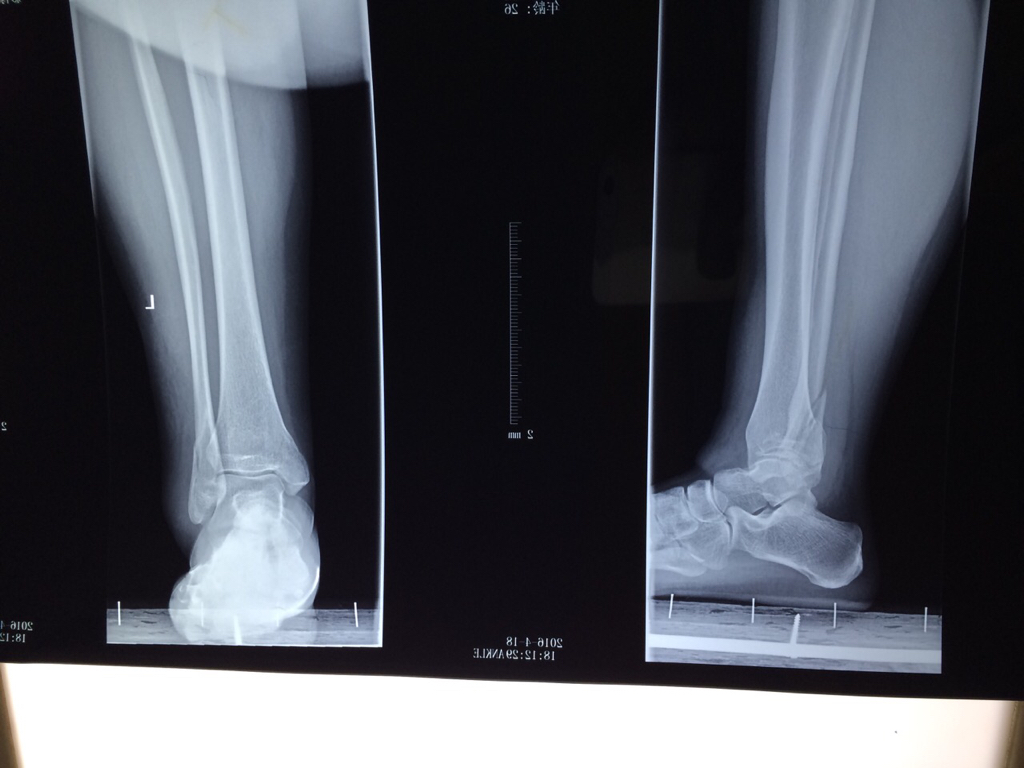

腓骨下端骨折

2岁小孩不慎被自行车碾压后致左胫腓骨下段骨折

左胫腓骨下端骨折

左侧腓骨下极撕脱骨折

【病例讨论】左胫骨下段开放性骨折 [病例帖]

小腿左胫腓骨中下段粉碎骨折,保守治疗.

腓骨骨折